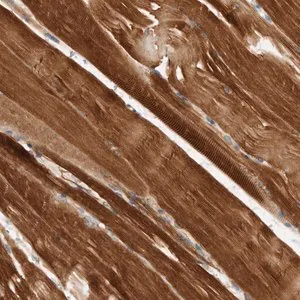

Prestige Antibodies® Powered by Atlas Antibodies 시리즈의 항체로, 토끼에서 생산된 AMPD1(adenosine monophosphate deaminase 1) 단백질에 대한 친화 정제 항체입니다. 완충된 수성 글리세롤 용액 형태로 제공됩니다.

AMPD1 유전자는 인간 염색체 1p13.2에 위치하며, N-말단 영역은 AMPD1의 기능에 필수적이고 C-말단 영역은 다른 아이소폼들 간에 보존되어 있습니다.